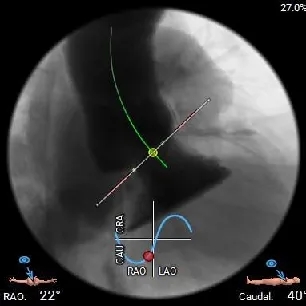

左右重叠体位:RAO 22° CAU 40° ,左冠切线位:LAO 23° CRA 17°;

工作体位

右窦中心